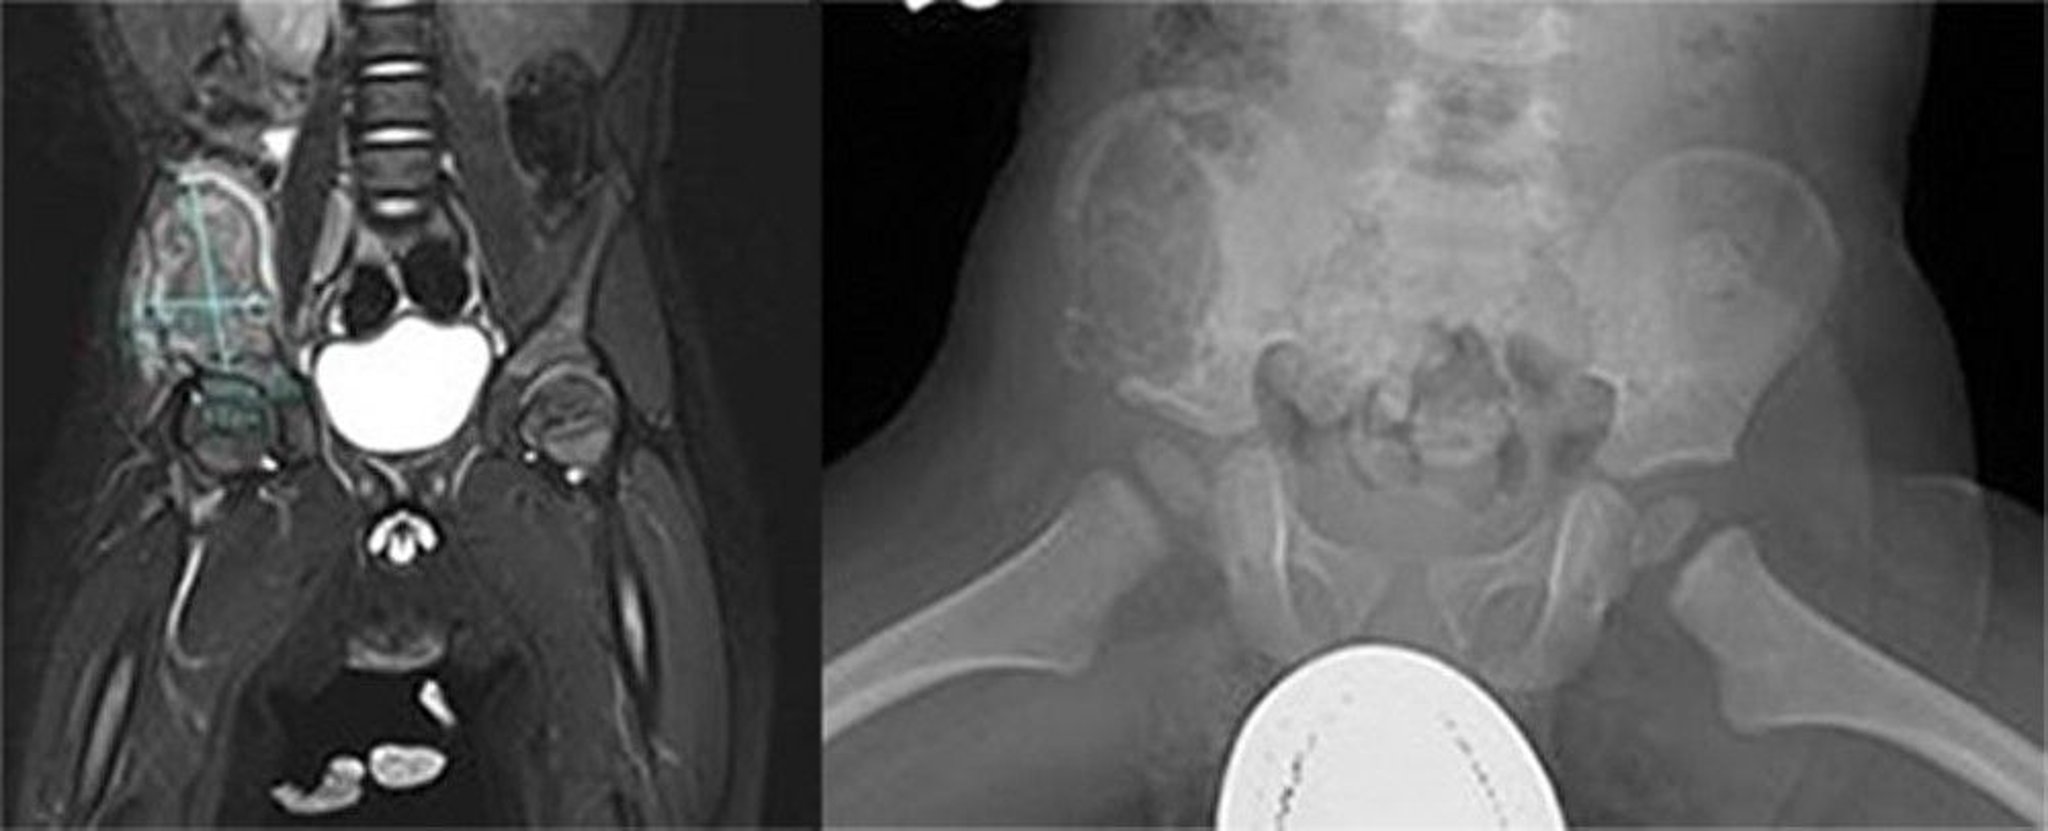

Langerhans Cell Histiocytosis (Pelvic Bone)

This image shows a large aggressive lesion within the right iliac wing. An MRI revealed the mass was heterogenous on T2 and low T1 signal with heterogenous enhancement of the mass and surrounding musculature with deviation of the right psoas muscle medially, suggesting an aggressive bone lesion (left). A large lytic lesion within the anterior and lateral ala of the ileum extending anterior and inferior to the ischium was visible on x-ray (right). There are expanded cortex and cortical irregularities. Biopsy was diagnostic for Langerhans cell histiocytosis.

Images courtesy of Carolyn Fein Levy, MD, and Jeffrey M. Lipton, MD, PhD.